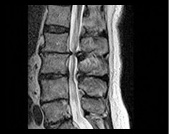

디스크탈출증이란? 손상된 디스크는 주변 신경을 자극하여 통증을 유발하는데 이것이 소위 ‘디스크’ 라 불리는 ‘디스크 탈출증’ 입니다. 척추뼈 속에는 우리 몸의 충격을 흡수하는 디스크 부위가 있습니다. 그러나 장기간 압박되거나 부상, 갑자기 강한 힘을 사용하는 움직임 등으로 인해 이 디스크는 돌출되기도 하고, 직업상 장시간 앉아서 작업하는 경우 파열되기도 합니다.

허리디스크의 증상

• 허리가 아프고, 다리가 저리고 당기는 증상입니다.

• 대개의 경우 허리가 먼저 아프고 엉치 부위가 아프며, 둔부에 통증을 느끼게 됩니다.

• 그러다가 얼마 지나서부터 한쪽 다리가 저리고 아프게 되며 허리에서부터 한쪽 다리로 당기는 통증이 발생하는 것이 보통입니다.

• 시간이 경과함에 따라 아픈 부위 다리의 감각이 둔해지거나, 또는 발가락 운동에 힘이 빠지게 되는 경우도 있습니다.

• 누워서 다리를 쭉 뻗은 상태에서 한쪽 다리를 올려보면 통증이 심해서 다리를 잘 올릴 수 없게 되며,다리를 들어 올리지 못하는정도가 심하면 심할수록 디스크의 탈출증의 정도가 심하다고 할 수 있습니다.